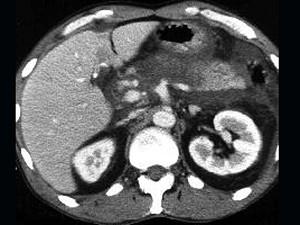

问题 女,45岁,急性上腹部持续性疼痛,程度剧烈,放射到胸背部,恶心、呕吐,白细胞计数增高,血尿淀粉酶升高,影像所见如图,最可能的诊断是 ( )

选项 A、胰腺癌 B、胰腺脓肿 C、急性出血坏死性胰腺炎 D、慢性胰腺炎 E、急性单纯性胰腺炎

答案 C